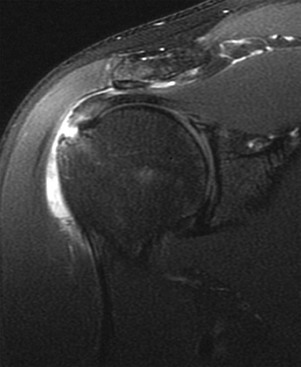

MRI findings include abnormal soft tissue in the rotator interval, obliteration of the subcoracoid fat triangle, and thickening of the coracohumeral ligament. Thickening of the joint capsule (normal is <4 mm) may also be seen in the region of the axillary pouch (Fig. 44-34). Inflammatory changes of the capsule may also be seen as increased T2-weighted signal adjacent to the capsule of the axillary pouch. The use of MRA may be helpful in establishing the correct diagnosis in two ways. First, a decreased joint volume of less than 10 mL will be noted, similar to conventional arthrography. Second, the contrast material will help outline and define the abnormal soft tissue in the rotator interval. Indirect MRA, however, appears to be most specific for establishing the diagnosis of adhesive capsulitis on the basis of imaging. Findings include enhancement of the abnormal soft tissues within the rotator interval combined with enhancement of the capsule and adjacent soft tissues in the region of the axillary pouch (see Box 44-4).132-134 However, Gondim Teixeira et al.135 recently reported high sensitivity and specificity with use of increased T2-weighted signal on fat-suppressed images in the capsule without the use of contrast material.

Adhesive capsulitis is a pathologic entity unique to the shoulder that is characterized by inflammation and thickening of the synovium. The inflammatory changes are most prominent in the areas of the capsule that lack reinforcement by the rotator cuff tendons, most notably the rotator interval and axillary recess. Women 40 to 70 years of age are most often affected; patients present clinically with the insidious onset of shoulder pain followed by progressive stiffness and weakness of the glenohumeral joint. The onset of symptoms is often related to a previous episode of minor trauma, but it may be idiopathic or associated with preexisting rheumatologic disorders or diabetes. At the time of clinical presentation, patients are often misdiagnosed with impingement syndrome or rotator cuff disease because the signs and symptoms broadly overlap with those of adhesive capsulitis. Physical examination demonstrates a painful restriction of motion of the shoulder in all directions, but the most pronounced restriction of motion usually involves external rotation of the humeral head (Box 44-4).

The clinical presentation and age distribution of patients with adhesive capsulitis overlap with those of rotator cuff disease, and as a result, imaging can play an important diagnostic role. No conventional radiographic signs are diagnostic of adhesive capsulitis, although radiographs may be helpful in excluding other sources of pain and decreased range of motion. Conventional arthrography demonstrates a small contracted joint capsule with a decreased joint volume of less than 10 mL. The axillary pouch appears small and contracted, and there is a lack of contrast material filling the long head of the biceps tendon sheath.